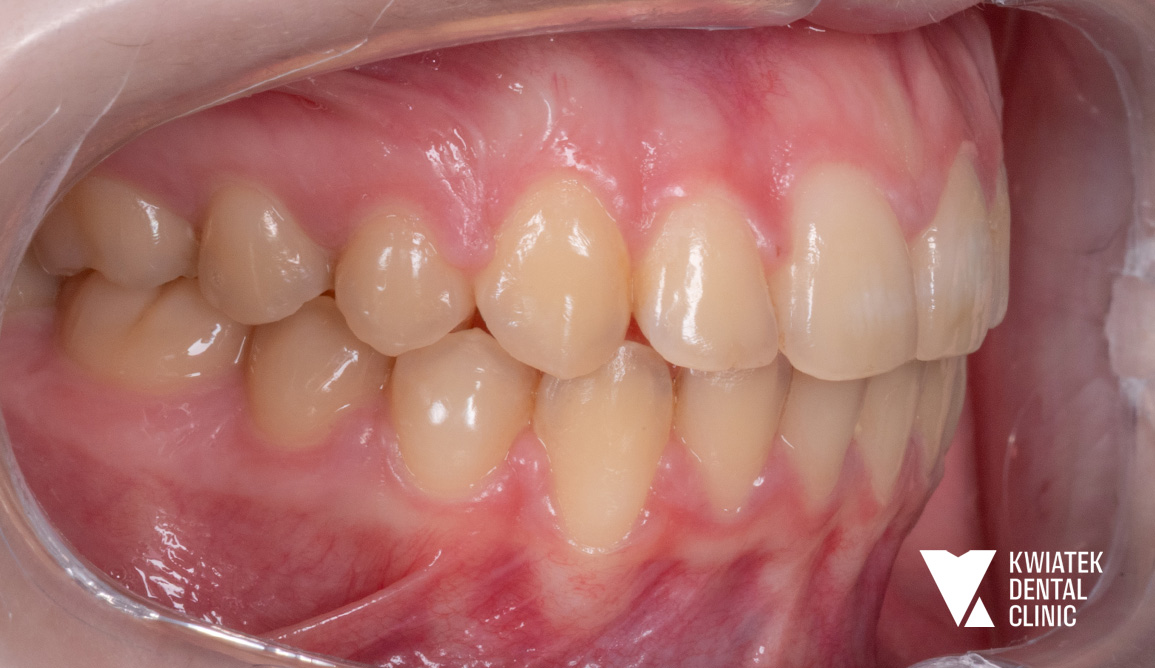

Leczenie rozpoczęto od szczegółowej konsultacji ortodontycznej oraz pełnej diagnostyki obejmującej zdjęcie pantomograficzne, cefalometryczne oraz skan wewnątrzustny.

W badaniu stwierdzono:

Już na etapie diagnostyki wskazano konieczność leczenia interdyscyplinarnego obejmującego zarówno ortodoncję, jak i intensywną poprawę higieny jamy ustnej.